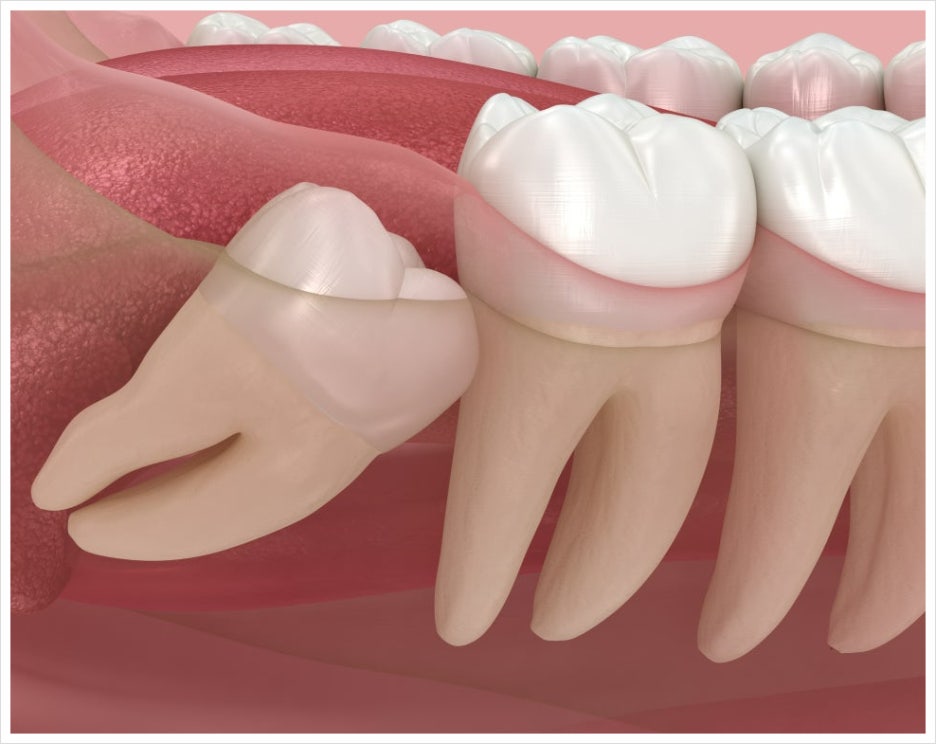

사랑니는 다른 치아가 다 맹출하고 난 뒤에 구강 내에서 가장 마지막으로 자라는 치아인데요.

공간 부족으로 인해 완전히 잇몸을 뚫고 나오지 못하거나 기울어지는 경우도 있고, 잇몸 속에 파묻혀 있는 등 생각보다 다양한 형태로 위치하고 있습니다.